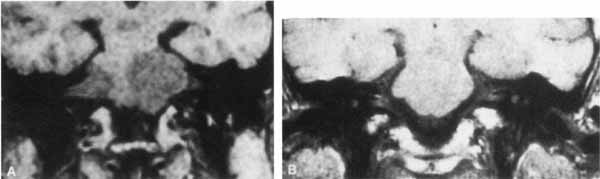

On CT scan, acoustic neuromas may be seen as enhancing masses in the internal auditory canal or cerebellopontine angle. For smaller tumors, gadolinium-enhanced MRI may be very helpful. On T1-weighted gadolinium images, neuromas may appear as uniformly enhancing masses, effacing the brain stem and cerebellum with extension into the internal auditory meatus or canal. On T2-weighted images these lesions appear hyperintense (Fig. 15).89 Treatment usually consists of microsurgical excision with the use of techniques that may provide complete removal of tumor and preservation of the facial nerve. Intraoperative facial nerve monitoring during acoustic neuroma surgery may improve the preservation of facial nerve function.90,91 Spontaneous recovery of facial function usually begins by 3 to 4 months after surgery and is typically finished by 1 year. Those palsies persisting beyond one year are likely to be permanent.92

Fig. 15 Magnetic resonance imaging of acoustic neuroma. A. Coronal section through pons showing bilateral acoustic neuromas in a patient with neurofibromatosis. B. Normal study of same area.